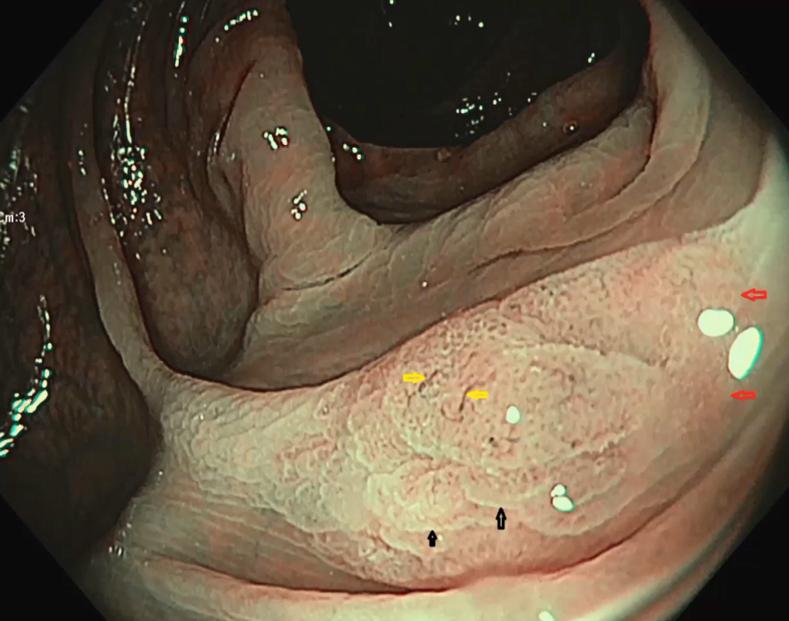

Endoscopic recognition of the sessile serrated polyp to cancer sequence.

VideoGIE. 2017 May 10;2(7):185-187. doi: 10.1016/j.vgie.2017.04.004. eCollection 2017 Jul.